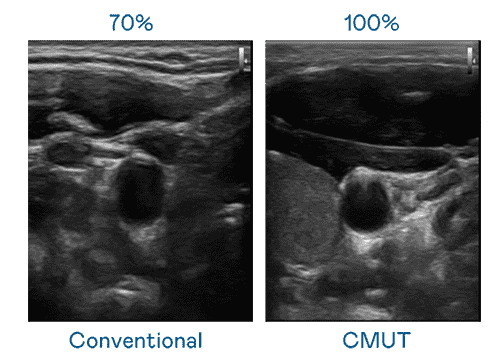

CMUT 技术是一种用电容式微机电元件来产生超音波讯号的技术。。与传统 PZT 压电式技术相比,,,,CMUT 频宽增加 30%,,,,更宽频的超音波讯号让影像解析度大幅提升,,是实现高影像品质医疗超音波扫描、、促进精准医疗发展的关键技术。。

大频宽带来超清晰影像

超音波影像的解析度高低,,首先取决于探头能发出的讯号频宽。。。28国际 CMUT 可提供高清晰的超音波讯号,,,,提供高频宽、、高灵敏度、、影像纹理细节更高的超音波影像,,协助医护人员缩短影像判读时间及利用精准的医疗影像进行诊断。。。